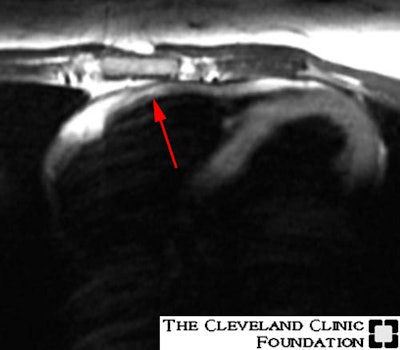

Arrhythmogenic Right Ventricular Dysplasia: Case 1

(Case courtesy of Dr. Scott Flamm, MD)Axial T1W images with a coronal saturation band through the left ventricle. The red arrows point to fatty infiltration within the myocardium of the high body (#1) and the low infundibulum (#2) of the right ventricle:

Image 1: